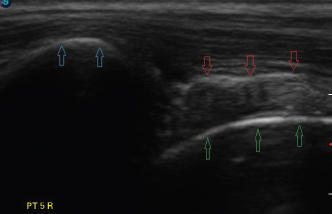

Fig. 4. Longitudinal ultrasound image of a biceps tendon (red arrows) post-transection, supraglenoid tubercle (blue arrows), and proximal humerus (green arrows). Note the laxity now present.

Ultrasound verification of complete tendon transection was demonstrated if the tendon remained lax proximally as it spanned the glenohumeral joint, even though the limb position had not changed (Fig. 4). The tendon’s appearance, following transection, could be compared to the images taken earlier, as needed. Longitudinal and transverse imaging was also performed over the transection site to demonstrate a complete absence of tendon fibers (Fig. 5). If incomplete transection was observed, the ultrasound probe was removed and the procedure repeated until complete transection occurred. On two occasions there was discordance between the second researcher’s assessment of the complete transection based on palpation, compared to ultrasound findings. On both those occasions, it was elected to proceed with dissection rather than resume the transection.